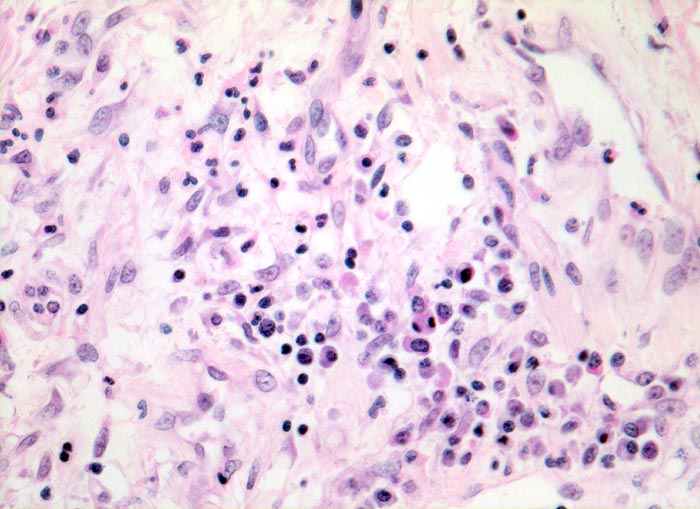

PathoPic – image database / PathoPic ID 4693 - Diffuser Alveolarschaden: proliferative Phase

Diffuser Alveolarschaden: proliferative Phase

Stark verbreiterte Alveolarsepten mit Fibroblastenproliferaten, Gefässeinsprossungen und gemischtem Entzündungsinfiltrat aus Lymphozyten, Histiozyten und Granulozyten.

Hospitalisation wegen akuter nekrotisierender Pankreatitis. Am zweiten Hospitalisationstag entwickelt der Patient ein ARDS (Adult Respiratory Distress Syndrome) mit rasch progredienter Dyspnoe und Tachypnoe, sowie einer Hypoxämie, welche im Verlauf auf Sauerstoffgabe nicht mehr anspricht. Das Thoraxröntgenbild zeigt bilaterale diffuse Verschattungen. Der Patient verstirbt trotz Intensivmassnahmen am 9. Tag nach Spitaleintritt am Multiorganversagen.

Histologie

320